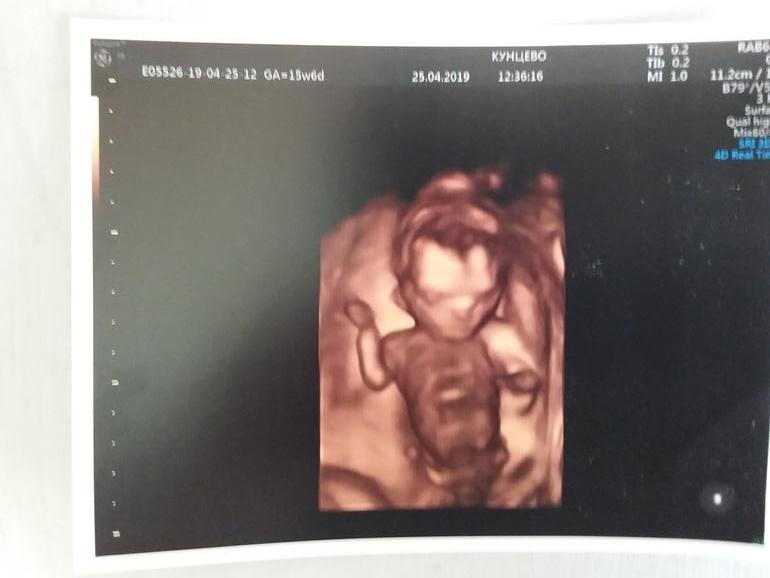

17 недель Второй скрининг Шевелюшки

Всё о нашей беременностиВот и дожили до 2 скрининга, еще раз подтвердили, что будет мальчик, сделали фоточку для папы, доолго сидел рассматривал сына, чуть не плакал, честно говоря!))) Уж не знаю, наверное рано судить, но мне показалось, что очень на папу похож.С малышом все замечательно, все измерения в норме, а вот ко мне претензии... Шейка укоротилась на 5 мм за 4 недели, стала 30 мм, ставят угрозу ИЦН, накрылись все мои планы на майские медным тазом! 😣 А планы были грандиозные, съездить к родителям, потом в тур по Европе, дэрэшечку отметить как следует...Но, кстати , почти не расстроилась, видимо у беременных какой-то блок все-таки стоит, я сейчас вообще ничего близко к сердцу не принимаю, кроме самого главного - человека в моем животике.Прописали ношпу, магний диаспорал и диванный образ жизни, через неделю узи.И УРА-УРА-УРАААА!!!!! Сегодня я в первый раз почувствовала настоящие шевелюшки, когда прилегла полежать прсле второго завтрака)))) Прям почувствовала, что он там поворачивается в течение несколько секунд, потом через минуту еще раз!)))) Счастье-то какое!!!!😄 Сидела с полными от слез глазами минут 10, вот они слезы счастья!))) Как же долго я этого ждала!)